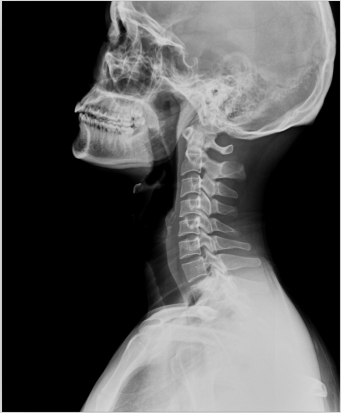

2、頸椎腰椎——最佳選核磁共振成像、次選CT

頸椎病、腰椎間盤突出等椎間盤疾病需要觀察椎間盤與相應(yīng)的神經(jīng)根,要想更好觀察這些軟組織,最優(yōu)選擇就是磁共振成像。同樣,對于關(guān)節(jié)、肌肉、脂肪組織檢查,腫瘤、炎癥、創(chuàng)傷、退行性病變以及各種先天性疾病的檢查,磁共振成像也是不錯的選擇。CT可以作為觀察脊椎骨質(zhì)增生、椎間孔狹窄的有力補(bǔ)充。